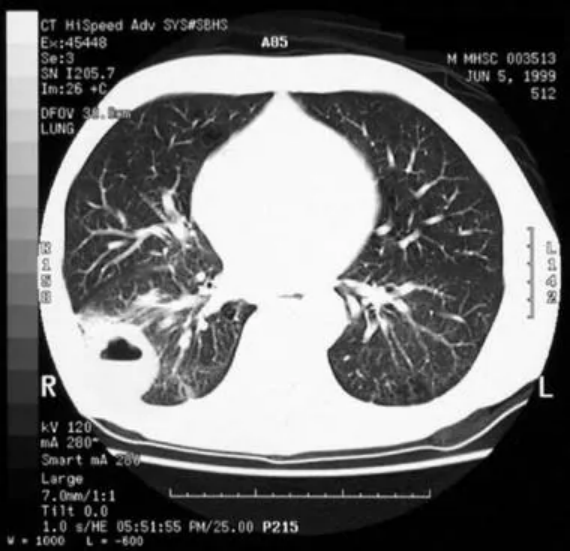

超过90%的患者恶性边缘呈结节状,边缘不规则和呈球形的结节为恶性肿瘤。此外,在恶性结节中空气支气管造影所见和伪空化(局部透明性)更为常见。下图所示的空化可能是恶性和良性病变的特征。

非小细胞肺癌。CT扫描显示气蚀和空气液位。

壁腔的厚度可能有助于区分良性和恶性病变。<1 mm的壁表示95%的患者为良性病变,>15 mm的壁厚度表示>80%的患者为恶性病变。